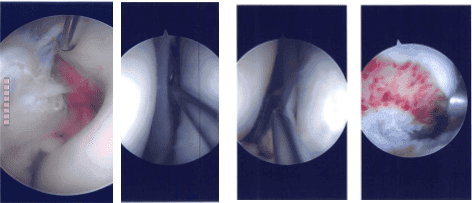

Intraoperative Arthroscopy Images

A medical entry portal was also made. There was grade 2 to grade 3 arthritis on the medial femoral condyle, which was cleaned by shaver. There was grade 2 to grade 3 arthritis on the patella, which was cleaned by the shaver, medial as well as lateral meniscus tear. Examination of the intercondylar notch there was 90% tear of the ACL, which was decided to be reconstructed and it was not repairable.

The graft was tightened with a tightrope on either end and found to be in an acceptable position and checked by an arthroscope. The tightropes were tied to each other, and the shuttling suture was removed. Final pictures were taken and saved.